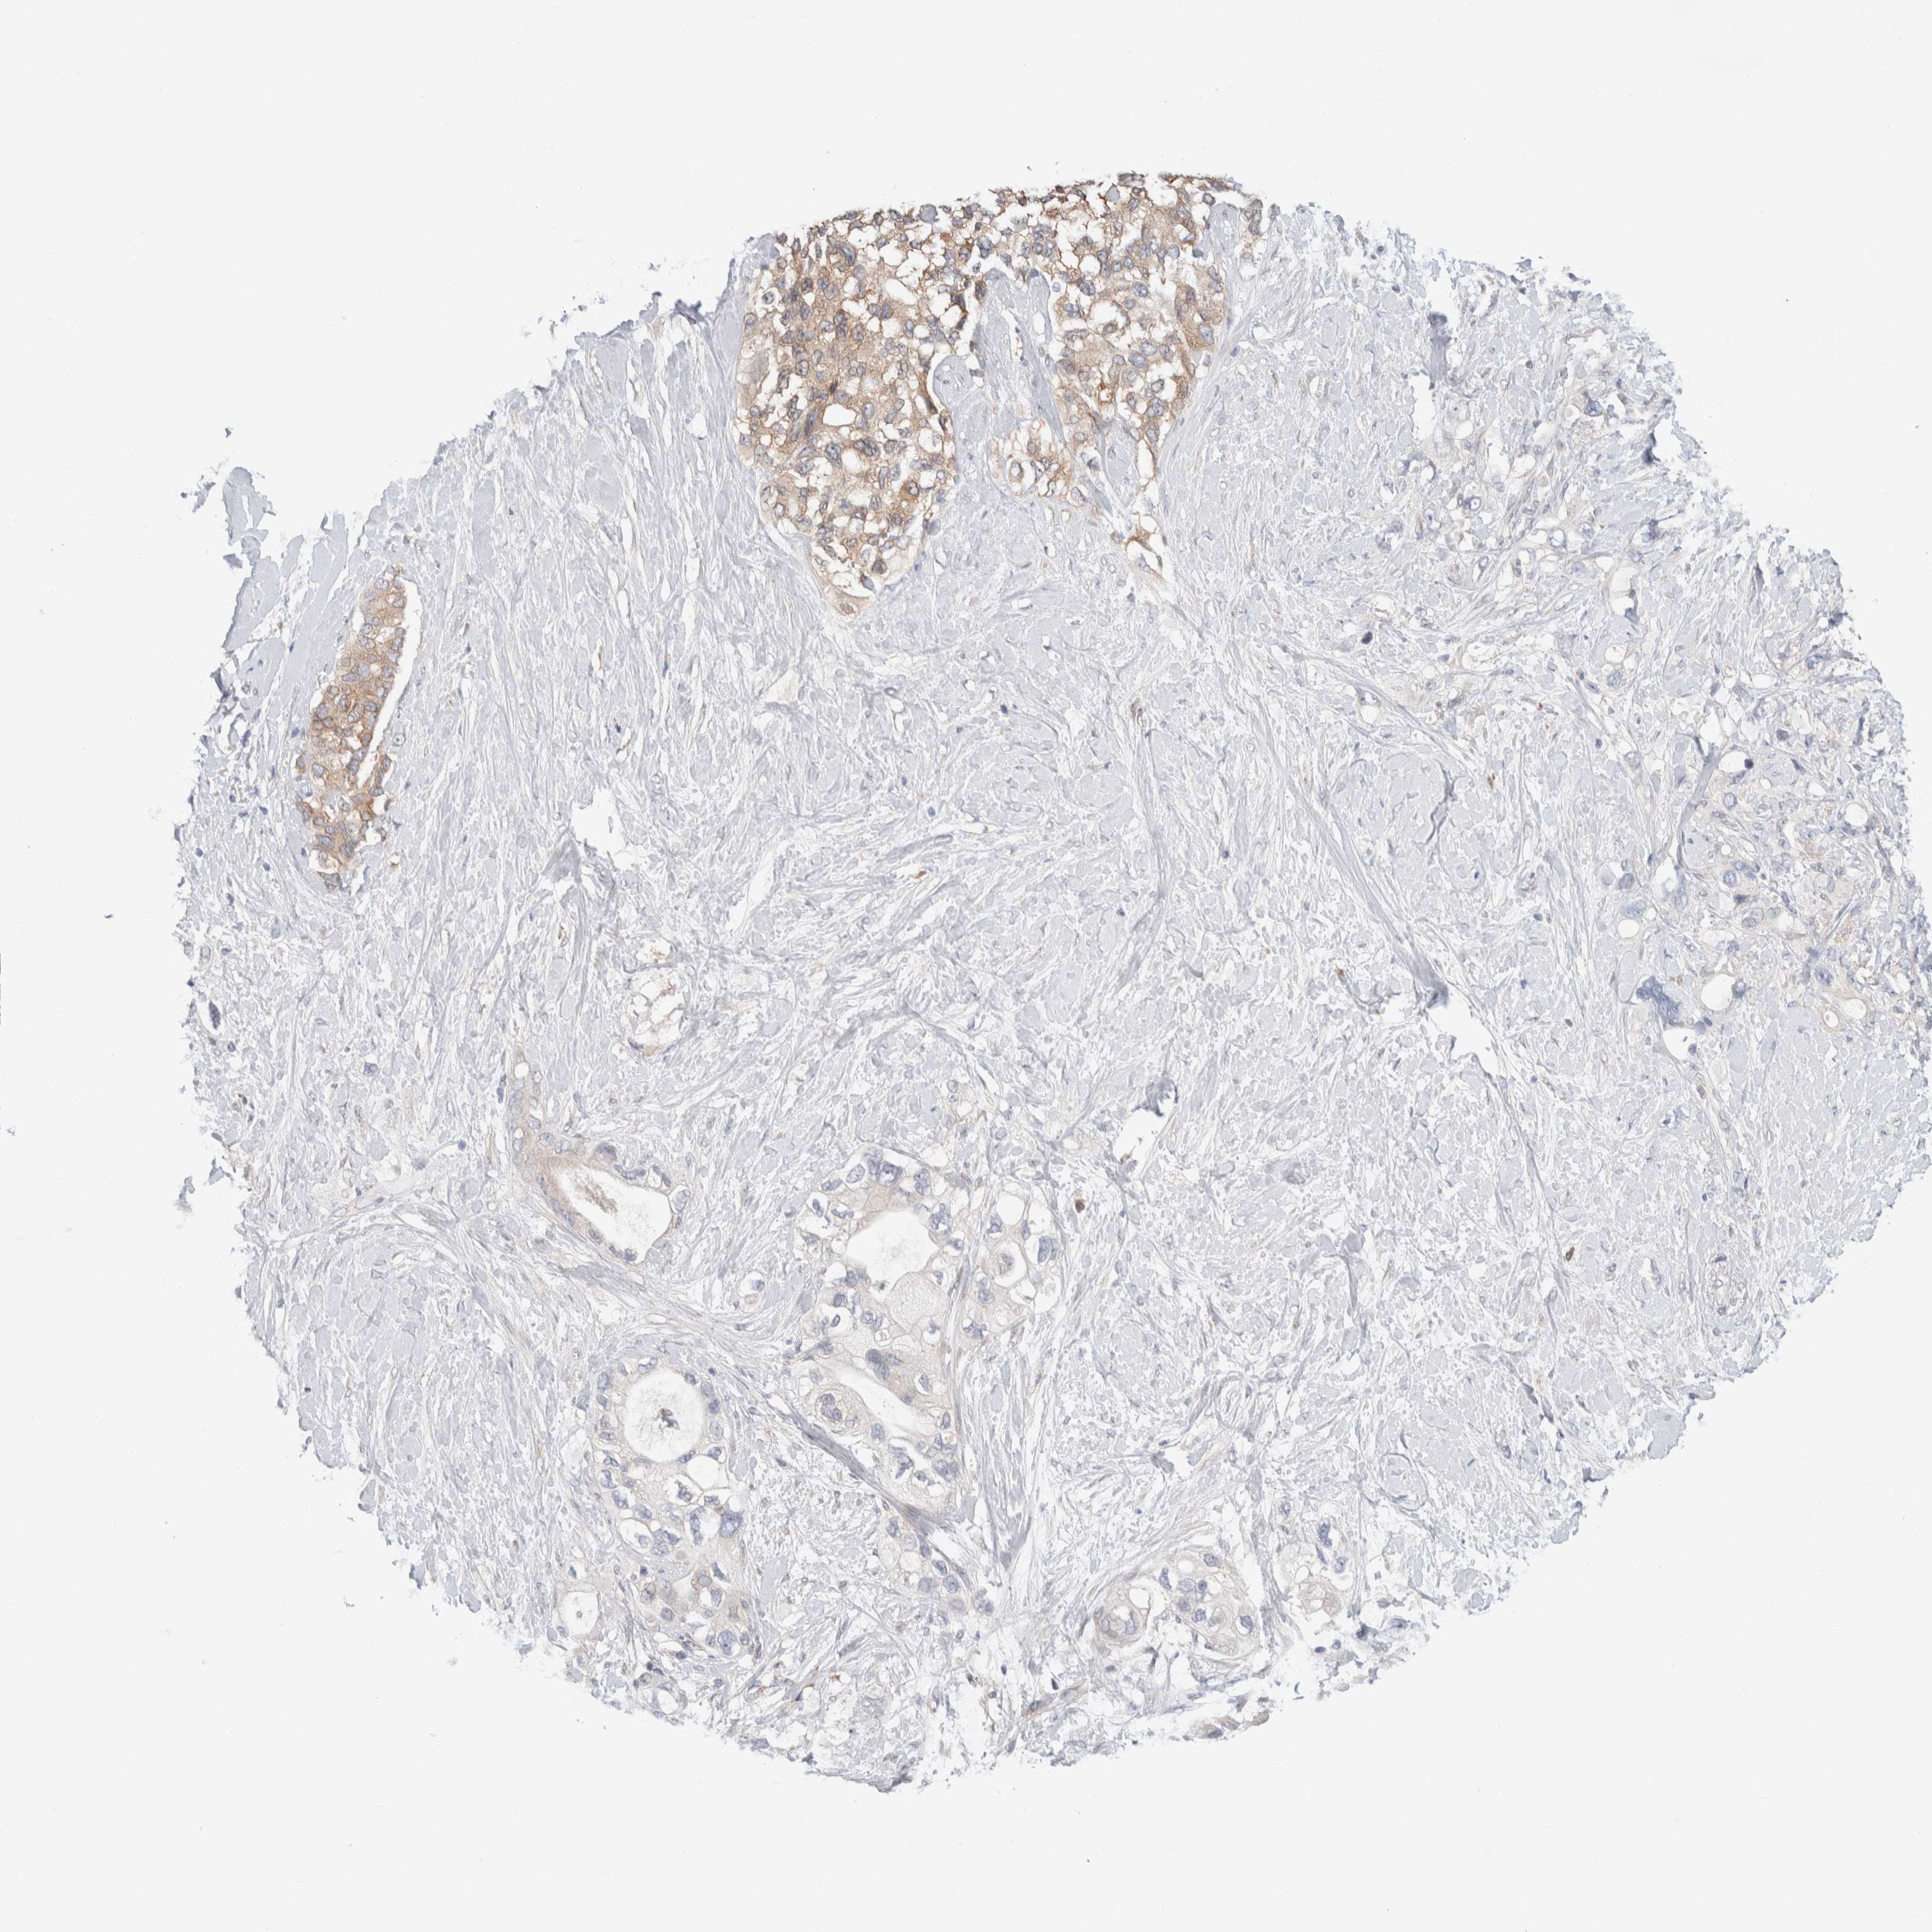

PANCREATIC CANCER - Protein expressioni

A mouse-over function shows sample information and annotation data. Click on an image to view it in a full screen mode. Samples can be filtered based on level of antibody staining by selecting one or several of the following categories: high, medium, low and not detected. The assay and annotation is described here.

Note that samples used for immunohistochemistry by the Human Protein Atlas do not correspond to samples in the TCGA dataset.

Antibody stainingi

Antibody staining in the annotated cell types in the current human tissue is reported as not detected, low, medium, or high, based on conventional immunohistochemistry profiling in selected tissues. This score is based on the combination of the staining intensity and fraction of stained cells.

Each image is clickable and will lead to virtual microscopy that enables deeper exploration of all samples and also displays staining intensity scores, fraction scores and subcellular localization as well as patient and tissue information for each sample.

Antibody HPA024406

Staining

High

Medium

Low

Not detected

Intensity

Strong

Moderate

Weak

Negative

Quantity

>75%

75%-25%

<25%

None

Location

Nuclear

Cytoplasmic/membranous

Cytoplasmic/membranous,nuclear

Adenocarcinoma, NOS